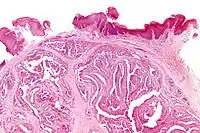

Micrograph of a papillary hidradenoma with the characteristic papillary structures and epithelium with apocrine snouts. A fragmented overlying epidermis is seen at the top of the image. H&E stain.

Micrograph of a papillary hidradenoma with the characteristic papillary structures and epithelium with apocrine snouts. A fragmented overlying epidermis is seen at the top of the image. H&E stain. a,b) Cells of lumina showed decapitation secretion similar to apocrine gland